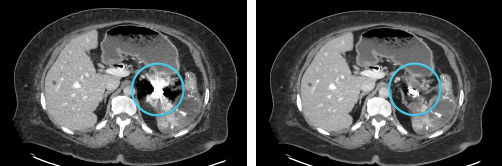

GSI MAR

Left: 40 keV; Right: 40 keV with GSI MAR. GSI Metal Artifact Reduction (GSI MAR) is a dual energy metal artifact reduction algorithm designed to reveal anatomic details obscured by metal artifacts. GSI MAR benefits for radiation oncology: reduced artifacts for more productive target delineation and dose calculation.